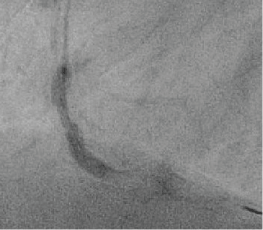

Figure 3: Ultra-high pressure balloon that remains inflated even after pressure-drop in the indeflator, indicating rupture. Balloon is still underexpanded in the proximal part. View Figure 3